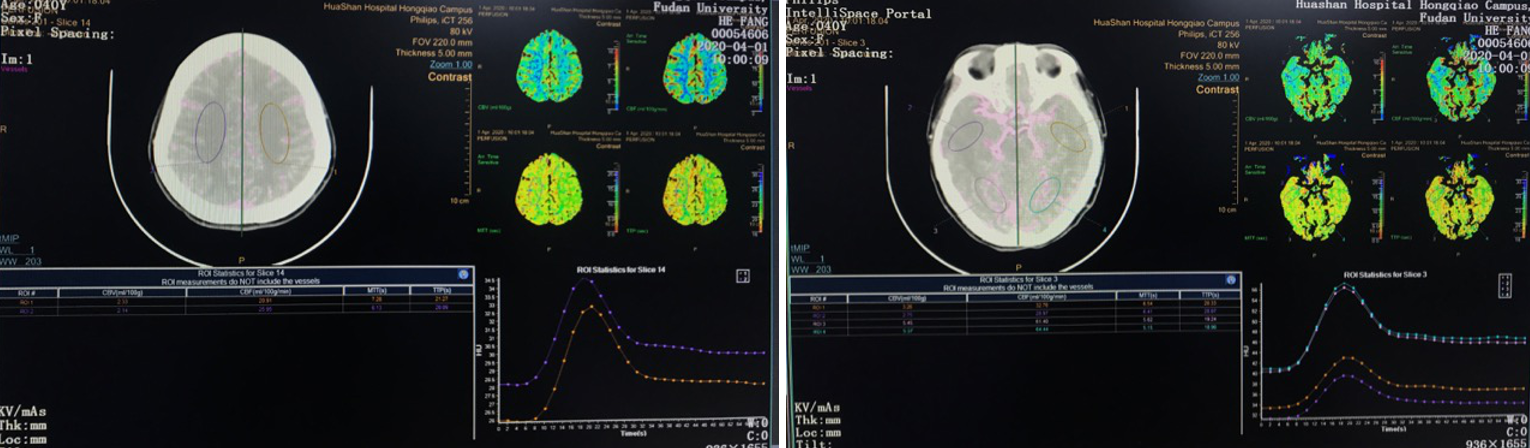

早查房时突发意识障碍。

备选方案:

脑室内血肿清除+动脉瘤切除+低流量搭桥。

在本例病例中,针对脑室内动脉瘤,我们首选血管内治疗栓塞脑室旁动脉瘤,因为血管过于迂曲尝试失败。术后出现脑室内出血,于是启动备选方案,急诊在磁共振导航下通过endoport辅助进行动脉瘤切除,同时部分清除脑室内血肿并放置脑室外引流,降低远期脑脑积水的风险。随着神经内镜的普及,深部的脑血管病变的治疗方案有了更多的选择,而充分的术前评估与周全的手术方案规划是手术安全与成功的基石。